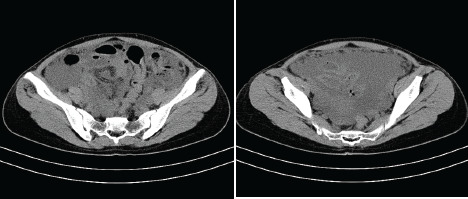

Objective: We present a case of a 31-year-old patient from Nepal, who was admitted through the emergency department of General Hospital Zabok, Croatia, with signs of acute abdomen, later successfully diagnosed and treated for ATB.